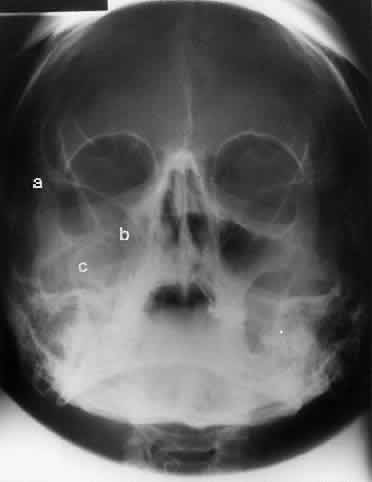

In an attempt to improve the visualization of the maxillary and ethmoid sinuses, in 1915 Waters and Waldron7 described a radiographic projection (Fig. 2) that eliminated the overlapping shadows of the dense petrous ridge of the temporal bone. Waters projection is created by placing the chin of the patient on the x-ray cassette with the canthomeatal line (the line that connects the lateral canthus and the external auditory meatus) at 37 degrees to 45 degrees.5,6 This orientation is accomplished if the nose of the patient is approximately 0.5 to 1.5 cm above the x-ray plate.7,8 A mnemonic is—the patient raises the chin up to sip water.

Fig. 2. A. Schematic showing positioning for a Waters projection. (CM, canthomeatal line; CR, central ray) B. Radiograph of a Waters projection. The petrous ridge lies below the maxillary sinus. (a, frontal sinus; b, medial orbital wall; c, innominate line; d, inferior orbital rim; e, orbital floor; f, maxillary antrum; g, superior orbital fissure; h, zygomatic-frontal suture; i, zygomatic arch) (A; Rao VM, Gonzalez CF: Plain film radiography and polytomography of the orbit. In Gonzalez CF, Becker MH, Flanagan JC [eds]: Diagnostic Imaging in Ophthalmology, pp 1–7. New York, Springer Verlag, 1986)

Waters view provides the best image of the maxillary antrum and good images of the orbital rim, orbital floor, zygomatic bones and arches, lesser wing of the sphenoid, and infraorbital foramen. This view is useful to the clinician in orbital floor fracture assessment because of the clear image of the orbital floor and the underlying maxillary sinus. The floor of the orbit should form a continuous radiographic line with the lateral wall of the orbit. Confusion can occur regarding the location of the orbital floor and its relationship to the orbital rim. The orbital floor is located inferior to the orbital rim not in the same plane, because of the orientation of the patient's head in Waters projection. A soft tissue density in the roof of the maxillary sinus or opacification of the floor of the sinus suggests an orbital floor disruption.